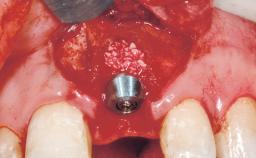

Type of Implants One-Piece

Bone Augmentation Horizontal|Staged

Soft Tissue Grafting Simultaneous

Bone Volume Deficient horizontally, requiring prior grafting